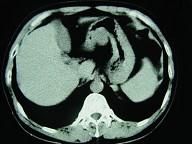

男,52岁,中上腹痛,影像检查如图,最可能的诊断是()A.慢肥厚性胃炎B.胃癌C.胃溃疡D.胃平滑肌瘤E.胃平滑肌肉瘤

问题 男,52岁,中上腹痛,影像检查如图,最可能的诊断是()

选项 A.慢肥厚性胃炎 B.胃癌 C.胃溃疡 D.胃平滑肌瘤 E.胃平滑肌肉瘤

答案 D